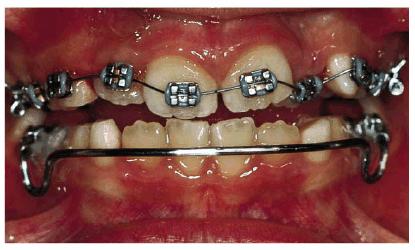

A female patient, 6 years, 7 months old.

PROBLEM: The patient's frontal view showed a serious bimaxillary

crowding with deviation of the midline. When teeth #7 and #10 erupted, crowding

problems greatly increased. Also, tooth #10 was in crossbite (Figure 27-9A).

Figure 27-9A: A serious bimaxillary crowding with deviation of the midline in a 6-year, 7-month-old female.

TREATMENT: After a

short observation period, while the lateral incisors erupted, the pediatric

dentist and the orthodontist initiated therapy. M and R were sliced, and a lip

bumper was applied to K and T. The occlusal surface rose to resolve the

crossbite of the upper left lateral incisor. The maxillary arch was treated orthodontically

to correct the alignment (Figure 27-9B).

Figure 27-9B: After a short observation period, the early orthodontic therapy is started.

RESULT: The patient underwent an early orthodontic treatment for 1 year

that achieved arch balance, improvement of esthetics, and health of the oral

tissues. Furthermore, the improved smile contributed to greater self-confidence

and an improved sense of well-being (Figures 27-9C and D).

Figure 27-9C and D: The patient's smile and the lower arch after the orthodontic treatment: good balance and esthetics are achieved.